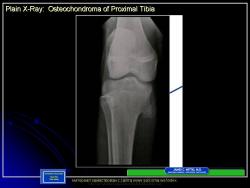

Иллюстрации из литературных источников.

Приложения:

14.N.Slayd15.JPG15.N.Slayd16.JPG16.N.Slayd17.JPG17.N.Slayd18.JPG18.N.Slayd19.JPG19.N.Slayd20.JPG1.1.Slayd20.JPG2.2.Slayd21.JPG3.3.Slayd22.JPG210.OH_.Slayd25.JPG